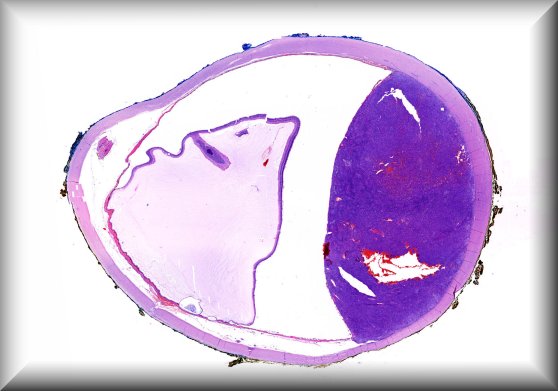

Dietmar Thal (Leuven): Eyeball resection for melanoma in an 83-year old male Alzheimer's disease patient |